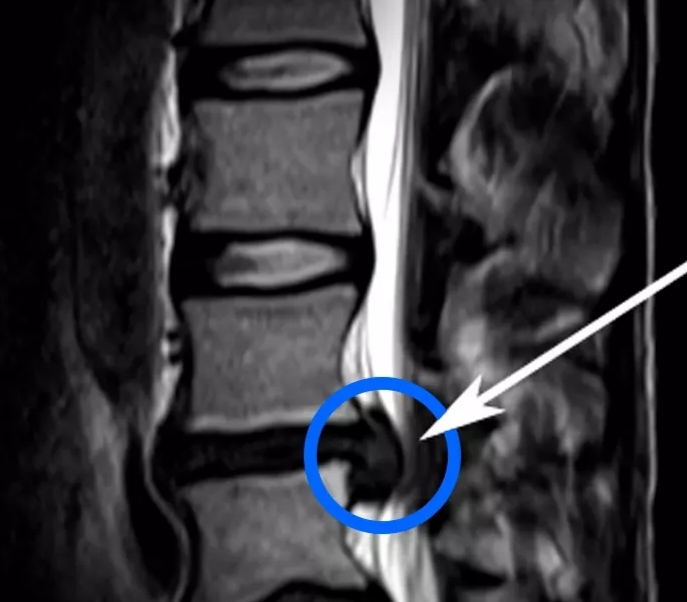

Spinal surgery is not always an answer for spinal pain. Heal your pain from inside out. Trust the best in pain relief industry. Book your appointment with our specialist Dr Gaurav Paiwal, Physio today. #avoidspinesurgery #healspinepain #painrelief